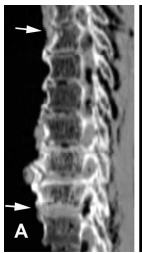

CT of the thoracic spine of mummified King Amenhotep III (1390–1352 BC) diagnosed with DISH

disease . Sagittal two-dimensional image showing continuous ossification of the anterior longitudinal ligament from the fourth to the ninth vertebrae (between arrows) associated with osteophytes and normal height of the intervertebral discs . Credit: Saleem at al.,DOI: 10.1002/art.38864

A diagnosis of ankylosing spondylitis was ruled out due to the absence of joint erosion in the lower back and pelvis area (sacroiliac joints) or fusion of sacroiliac joints or of small joints between the vertebra in the spine (facet joints) on the CT scans of the mummies. Signs of DISH were found in four Pharaohs (Amenhotep III—18th Dynasty; Ramesses II, his son Merenptah, and Ramesses III—19th to early 20th Dynasties).